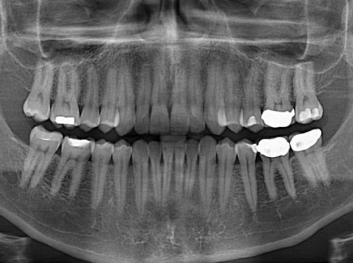

損壞的牙齒如何自我修復?近日,來自哈佛大學和諾丁漢大學的研究人員研發(fā)了能夠刺激牙齒干細胞再生的新型生物材料,而這種新材料研發(fā)成功的背后,正源于他們對牙齒如何實現(xiàn)自我修復這個課題的不斷探索。

據(jù)美國期刊《大眾科學(Popular Science)》報道,此種新型生物材料,不僅可以有效地取代傳統(tǒng)補牙填充物,刺激牙齒干細胞再生,患者也有望無需再接受根管治療,使蛀牙患者免除牙根感染或牙髓壞死的苦惱,一個全新的牙齒治療時代即將來臨。

Adam Celiz,是來自諾丁漢大學的研究人員,他和同事開發(fā)的這種新型合成生物材料,能刺激干細胞在牙髓部的生長。與普通材料一樣,這種合成材料被填充到牙齒并用UV光硬化。

在體外測試中,材料刺激干細胞進入牙本質的增殖和分化速度,促進形成牙齒骨組織。研究人員認為,一旦材料在受損牙齒中應用,這些干細胞可以自動修復來自填充物上的損壞。在本質上,該生物材料將使牙齒自愈。

在未來,Adam Celiz說,可再生材料能制成各種填充物以便受損牙齒的自身治愈,降低補牙失敗率,甚至會消除大部分人對根管治療的需要。